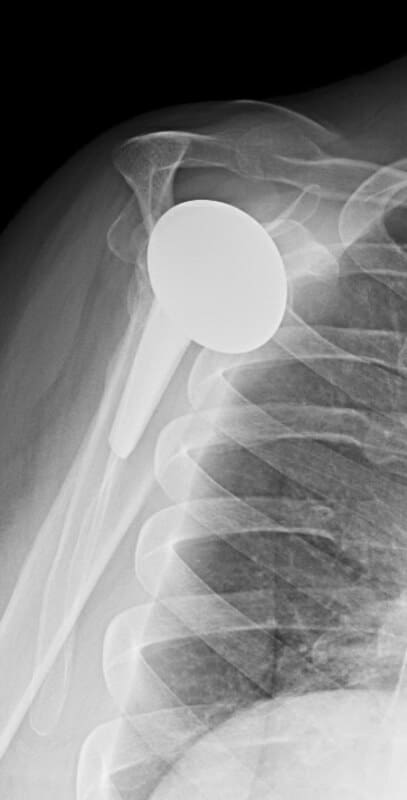

DePuy, Inhance